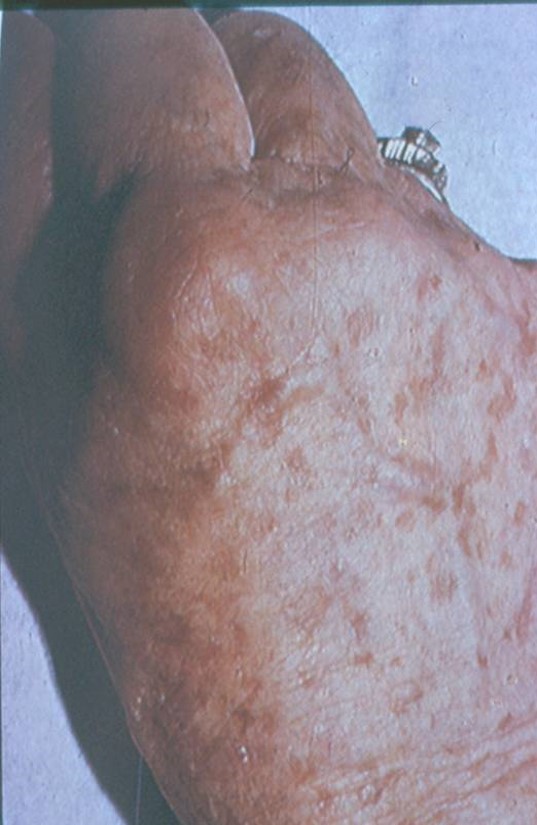

What disease process is pictured below?

Acanthosis Nigricans